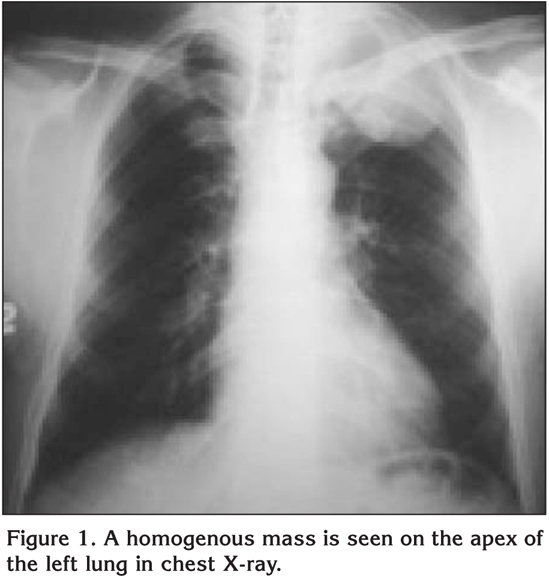

A 47-year-old male patient with chest pain complaints for 4 months and presenting effort dyspnea was admitted to our clinic. There was no pulmonary disease or tuberculosis in his clinical background. Although for 25 years he smoked 1 package of cigarettes a day, this habit had completely ceased 4 months before. In physical examination, the left hemithorax was more convex than the right hemithorax. There was no chest mass. There was an inspiratory rale on the right chest wall. Other examinations were normal. In laboratory analysis the results were white blood cell count (WBC) 11.400 KU/L, erythrocyte sedimentation rate (ESR) 39 mm/hour, antistreptolysin O (ASO) 260 IU/mL, C-reactive protein (CRP) 27.4 mg/L, serum calcium (Ca) 10.6 mg/dL, alanine aminotransferase (ALT) 87 mg/dL, aspartate aminotransferase (AST) 53 mg/dL, gamma glutamyltransferase (GGT) 88 U/L, lactate dehydrogenase (LDH) 596 U/L, creatin phosphokinase (CPK) 1086 U/L, creatine kinase MB (CK-MB) 37 U/L, and alkaline phosphatase (ALP) 382 U/L. Alpha-fetoprotein (AFP), cancer antigen (CA)-125, CA-15-3, CA-19-9, and carcinoembryonic antigen (CEA) results were normal. Evaluation through electrocardiography (ECG) evidenced Wolf Parkinson White syndrome. Chest X-ray revealed an increase of homogeneous density at the left upper lung lobe (Figure 1).

Figure 1